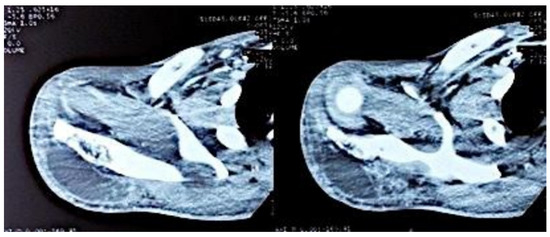

Figure 4. Axial sections of the shoulder CT scan, showing the deltoid collection.

Computed tomography of the right shoulder showed a lytic lesion of the right scapula with cortical rupture associated with scapular osteomyelitis (Figure 3, Figure 4 and Figure 5). The lesion was complicated by a deltoid abscess measuring 75 × 29 mm and extending over 105 mm (Figure 4), without joint effusion.